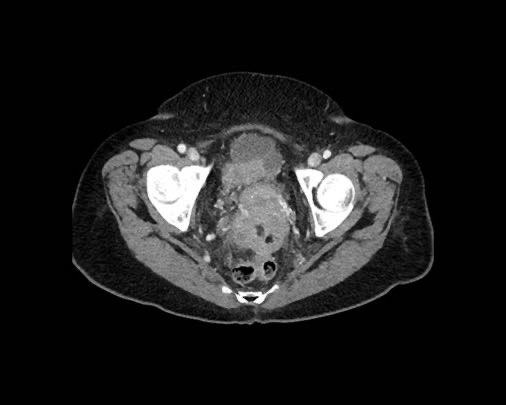

Ca lâm sàng 2

Cuộn qua các lát cắt.

Bạn có thể phát hiện tất cả các tổn thương cấy ghép phúc mạc không?

.jpeg)